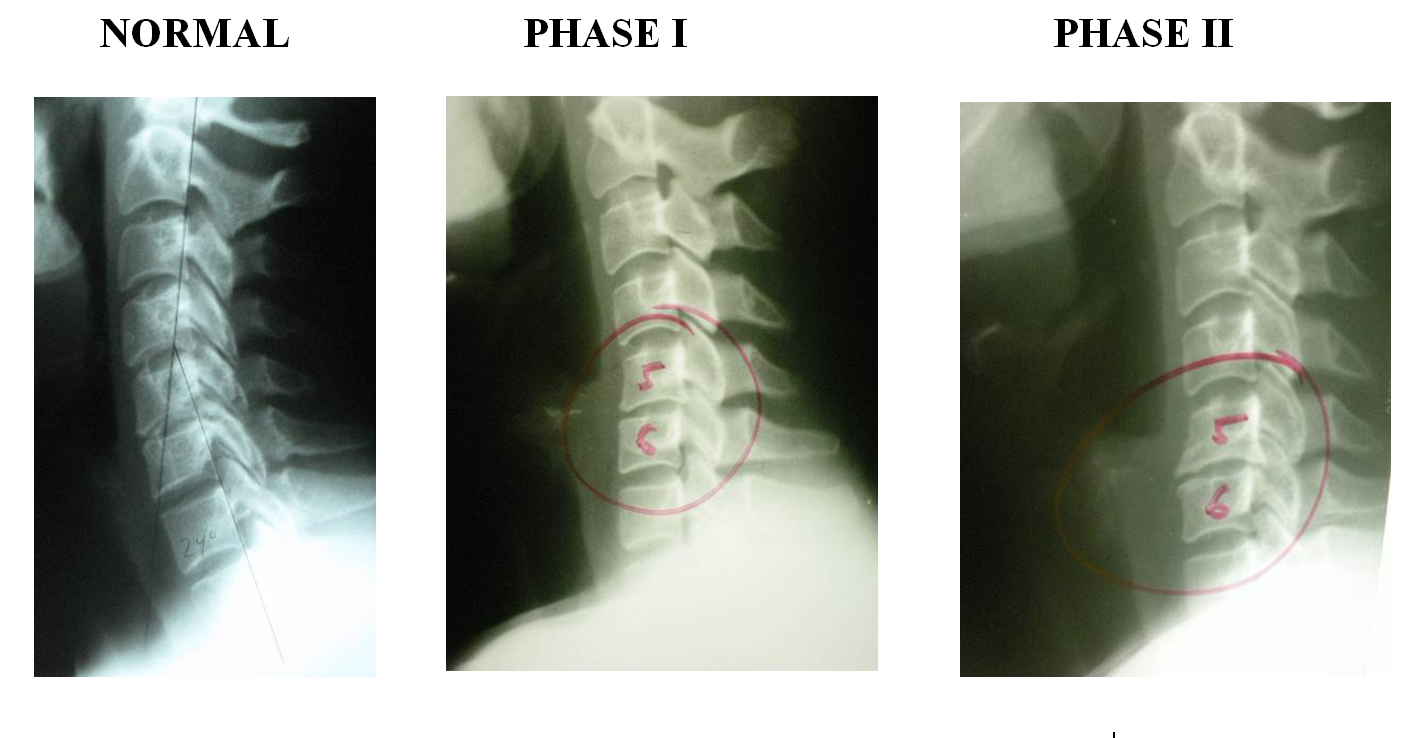

From www.dmchiropractic.my

It's Just a Little Arthritis…Right? DMChiropractic Arthritis In Neck Surgery learn about the causes, symptoms, diagnosis and treatment of cervical spondylosis, a common condition that affects the neck joints and disks as. learn about neck arthritis, a common condition that causes pain, inflammation, and stiffness in the neck. cervical spondylosis is a condition that affects the bones, disks, and joints of the neck, causing pain, stiffness, and. Arthritis In Neck Surgery.